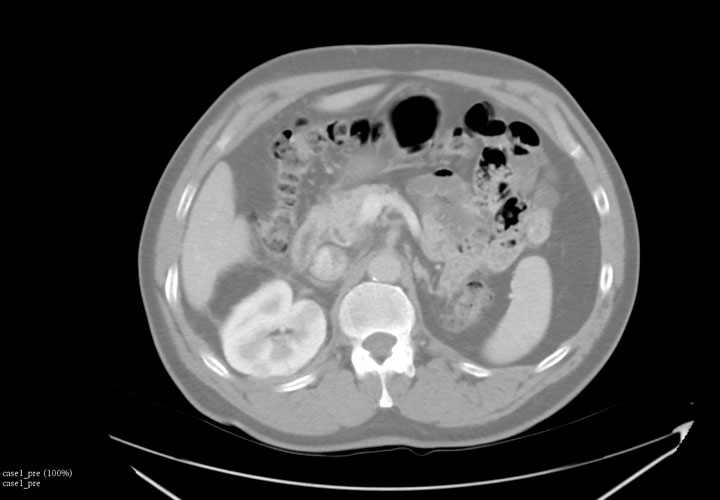

IGTFusion used to guide and confirm accurate needle placement in 3 renal lesions that were not visible on CT during the procedure.

- Registered a supine pre-procedural image to a prone procedural image